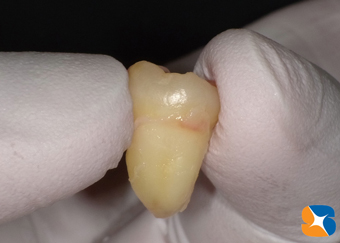

抜歯開始から30分後、無事に抜歯できました。予想通り、歯の頭の引っ掛りと、根の変形が、時間を費やした原因でした。

この角度から見ると、歯の根は変形していません。

しかし、角度を変える見ると、歯の根の先端がかなり変形しています。この様に変形した親知らずを抜歯するには、特殊な器具やテクニックが必要となります。